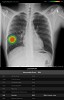

الرعاية الصحية | الثلاثاء 23 يونيو, 2020 3:38 صباحاً

قدمت "جنرال إلكتريك للرعاية الصحية" اليوم "منظومة العناية الصدرية"، وهي مجموعة برمجية من ثماني خوارزميات للذكاء الاصطناعي قائمة على حلول "لونيت إنسايت" لتصوير الصدر ...